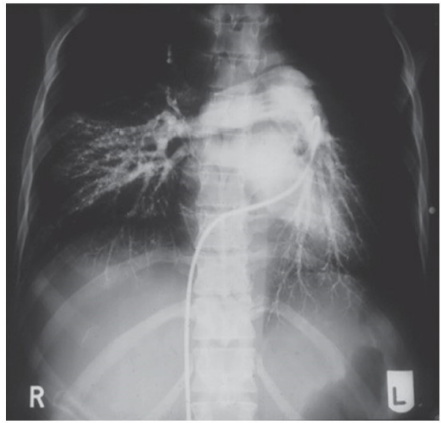

Foi solicitada uma angiotomografia com o resultado a seguir: